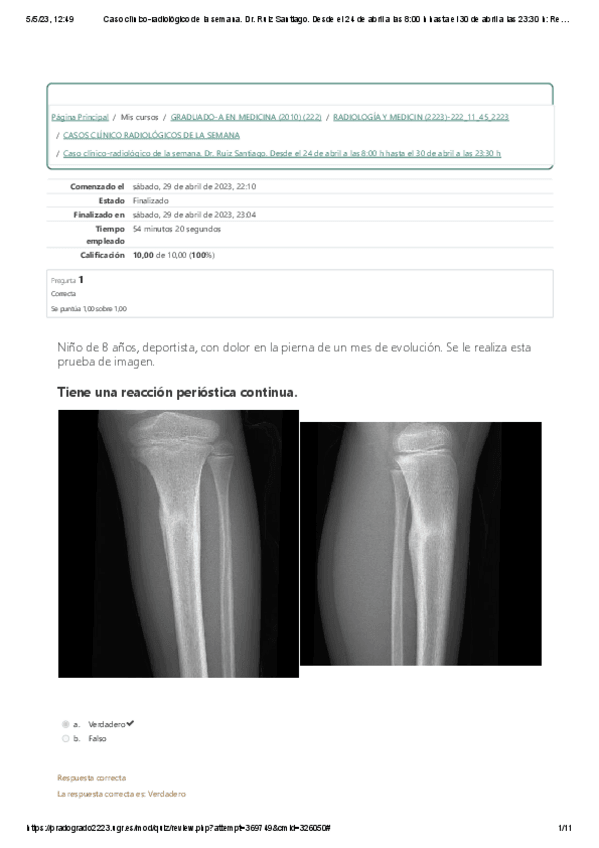

CASO CLÍNICO RADIOLÓGICO DE LA SEMANA. Músculo-esquelético. Dr. Ruiz Santiago.

12 páginas